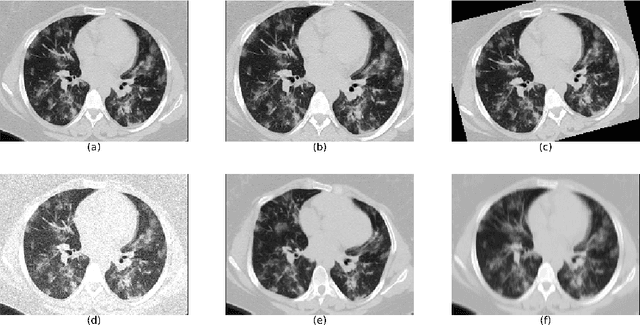

Abstract:The automatic assignment of a severity score to the CT scans of patients affected by COVID-19 pneumonia could reduce the workload in radiology departments. This study aims at exploiting Artificial intelligence (AI) for the identification, segmentation and quantification of COVID-19 pulmonary lesions. We investigated the effects of using multiple datasets, heterogeneously populated and annotated according to different criteria. We developed an automated analysis pipeline, the LungQuant system, based on a cascade of two U-nets. The first one (U-net_1) is devoted to the identification of the lung parenchyma, the second one (U-net_2) acts on a bounding box enclosing the segmented lungs to identify the areas affected by COVID-19 lesions. Different public datasets were used to train the U-nets and to evaluate their segmentation performances, which have been quantified in terms of the Dice index. The accuracy in predicting the CT-Severity Score (CT-SS) of the LungQuant system has been also evaluated. Both Dice and accuracy showed a dependency on the quality of annotations of the available data samples. On an independent and publicly available benchmark dataset, the Dice values measured between the masks predicted by LungQuant system and the reference ones were 0.95$\pm$0.01 and 0.66$\pm$0.13 for the segmentation of lungs and COVID-19 lesions, respectively. The accuracy of 90% in the identification of the CT-SS on this benchmark dataset was achieved. We analysed the impact of using data samples with different annotation criteria in training an AI-based quantification system for pulmonary involvement in COVID-19 pneumonia. In terms of the Dice index, the U-net segmentation quality strongly depends on the quality of the lesion annotations. Nevertheless, the CT-SS can be accurately predicted on independent validation sets, demonstrating the satisfactory generalization ability of the LungQuant.